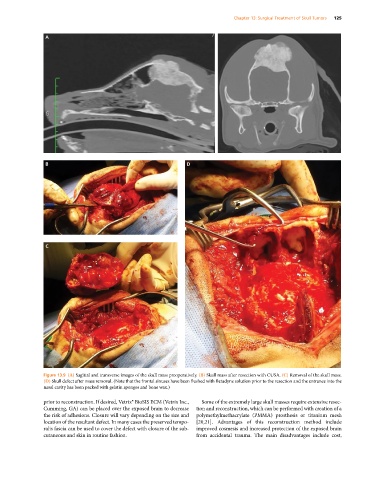

Figure 13.9 (A) Sagittal and transverse images of the skull mass preoperatively. (B) Skull mass after resection with CUSA. (C) Removal of the skull mass.

(D) Skull defect after mass removal. (Note that the frontal sinuses have been flushed with Betadyne solution prior to the resection and the entrance into the

nasal cavity has been packed with gelatin sponges and bone wax.)